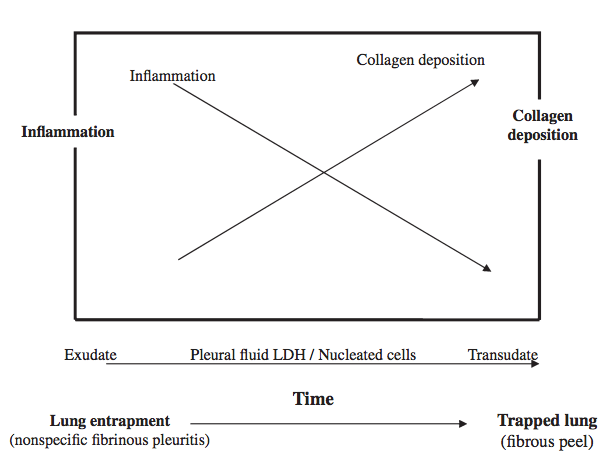

4/Lung entrapment is when the lung cannot fully expand due to an active disease that restricts the expansion of the lung and/or visceral pleura. This is typically associated with an exudative effusion. @tony_breu @KevinSwiatek

5/ Trapped lung is when the lung cannot expand due to a remote inflammatory condition that leaves a collagenous or fibrinous peel on the viscera pleura that prevents lung expansion. The pleural fluid can be transudative or exudative. @scall1200 @cderekleiner @rva_IntMedPD

12/In trapped lung, the fibrotic process affecting the visceral pleura causes an increase in the negative pleural pressure resulting in fluid accumulation and reduction in the removal of fluid by pleural lymphatics. @UpToDate @gsmartinmd @jackpenner